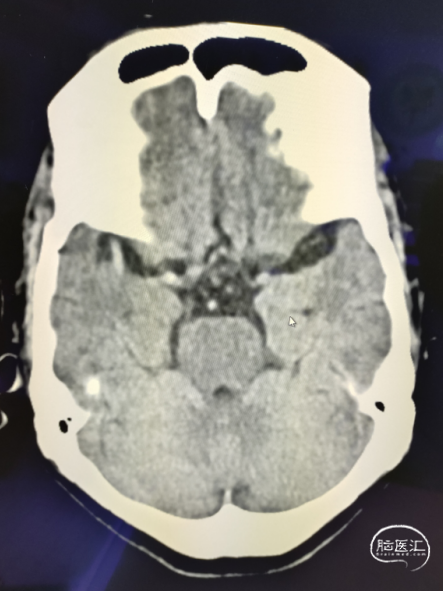

颅脑NCCT见右侧大脑总动脉高密度征,ASPECTS评分10分。

术前